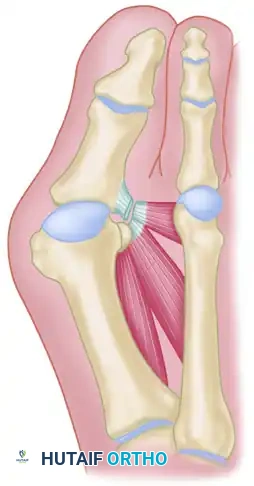

However, it is critical to understand the biomechanical trade-offs inherent to this procedure. Because the varus alignment of the first metatarsal is not directly corrected via osteotomy, maintaining the correction of the hallux valgus relies heavily on meticulous soft tissue reconstruction and postoperative scar tissue formation (encapsulation). Historically, complications such as "cock-up" toe deformity, transfer metatarsalgia, and recurrent valgus have been emphasized in the literature. These historical pitfalls often stemmed from over-resection of the phalanx, failure to stabilize the joint with Kirschner wires, or poor patient selection. In contemporary orthopedic practice, when patients are selected carefully and modern technical modifications are employed, complications are uncommon, and patient satisfaction is remarkably high.

Surgical Warning: The Keller procedure inherently destabilizes the intrinsic musculature of the hallux by detaching the insertion of the flexor hallucis brevis (FHB) and the adductor hallucis. Meticulous capsulorrhaphy and temporary axial K-wire fixation are absolute requirements to prevent postoperative dorsal subluxation (cock-up toe) driven by the unopposed pull of the extensor hallucis longus (EHL).